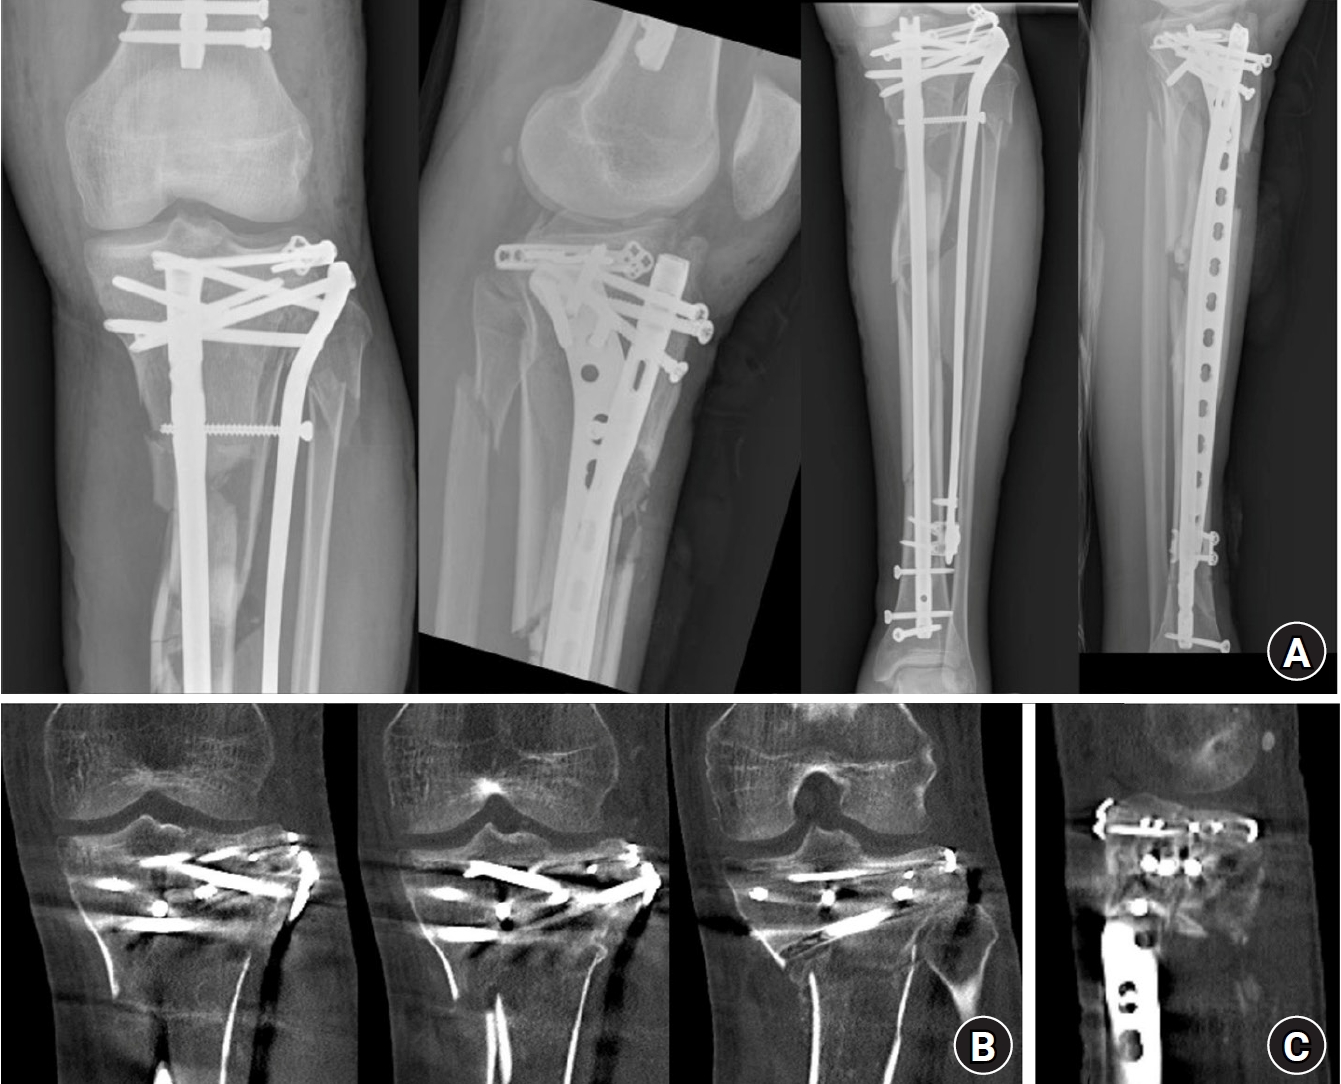

Fig. 3.

Postoperative plain radiographs and computed tomography (CT) images. (A) Postoperative plain radiograph. (B) Axial CT image confirming that screws from the rim plate did not interfere with the intramedullary nail trajectory. (C) Coronal CT image after fixation. (D) Sagittal CT image after fixation.

The procedure started by placing a rim plate to convert the tibial plateau fracture into a single articular segment. The surgical approach was chosen based on the fracture pattern. The patient had posterolateral and anteromedial tibial plateau fractures. To address the posterolateral fracture, a modified anterolateral approach was employed, extending through the space between the fibular collateral ligament (FCL) and the posterolateral plateau rim [7,8]. The anteromedial fracture was approached through an anteromedial incision of approximately 5 cm, extending from the proximal medial open wound. Long incisions were not required, as the exposure was sufficient for fracture reduction and rim plate placement. The medial collateral ligament was incised longitudinally at the fracture site to confirm intraarticular reduction. The posterolateral plateau fracture was reduced using a colinear clamp. A 2.7-mm variable-angle locking compression plate (VA-LCP; Variable Angle LCP Forefoot/Midfoot System 2.4/2.7, Synthes GmbH) was contoured and inserted into the posterolateral space beneath the FCL. The contoured plate and posterolateral fragment were pressed together with a pointed reduction bone clamp (Fig. 2A and 2B). To maintain compression, a 2.7-mm cortical screw was inserted into the most anterior hole, followed by 2.7-mm locking screws to secure the plate and connect the posterolateral fragment with the anterolateral main fragment at the plateau rim. On the anteromedial side, another 2.7-mm VA-LCP was contoured and positioned over the medial collateral ligament. A pointed bone reduction clamp was used to achieve medial-to-lateral compression, and 2.7-mm locking screws were inserted. This construct restored the tibial plateau as a single segment (Fig. 2C and 2D). In these procedures, care was taken to avoid directing screws toward the anterior center, which could obstruct IM nail passage. However, most screws—being oriented nearly perpendicular to the cortical surface and positioned within the allowable variable screw angulation of up to 30°—generally do not interfere with the trajectory of the IM nail. Therefore, it was sufficient to ensure that screws inserted through the anterior holes of the plate did not point excessively anteriorly. Once the plateau was stabilized as a single segment, IM nailing was performed through the suprapatellar approach to minimize the displacement of the proximal fragment. To prevent the displacement of the plateau segment during nail entry, both the tibial tuberosity and posterolateral aspect were secured with a pointed bone reduction clamp (Fig. 2E). During nailing, overall lower limb alignment was confirmed using the alignment rod before screw fixation. Only three cancellous screws could be inserted into the proximal segment. Additional anterolateral tibial plating was performed to improve the stability of the construct. A 4.5-mm LCP Proximal Tibia Plate (Synthes GmbH) was positioned using a MIPO technique. Fine adjustment of the plate position enabled linkage with the IM nail, a process that was technically straightforward. A drill sleeve was inserted through the proximal aiming arm of the IM nail (Expert Tibia Nail, Synthes GmbH), and the plate was adjusted to precisely align with the drill sleeve. Subsequently, 5.0-mm interlocking screws were inserted through the plate holes, connecting the transverse locking hole and the oblong slot of the IM nail to link the nail and plate (Fig. 2F and 2G). More 5.0-mm locking screws were added to the proximal holes of the plate to secure it to the proximal tibial section. For distal fixation, one 4.5-mm cortical screw and several 3.5-mm locking screws were inserted using a 3.5-mm locking attachment plate (Synthes GmbH). This was performed to avoid interference with the IM nail, completing the final fixation. Finally, the open wounds on the anteromedial aspect of the tibia were closed directly because no medial plate was applied. Postoperative plain radiographs and computed tomography (CT) images are shown in Fig. 3.